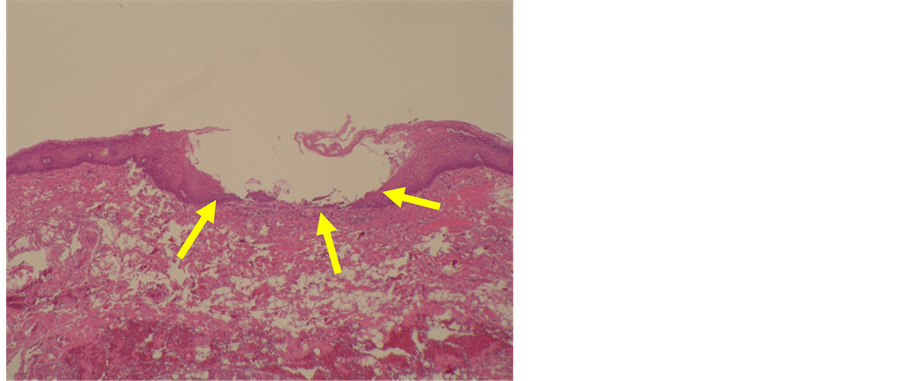

Biopsy was conducted during the initial consultation under the clinical diagnosis mentioned above. Epithelial peeling was observed from directly above the basal layer to the stratum spinosum (Figure 2), leading to a diagnosis not histopathologically conflicting with pemphigus vulgaris. Under direct immunofluorescence, mild deposition of immunoglobulin IgG and complement C1q was observed along the basal membrane. However, deposition of IgG corresponding to the epithelial cell membrane was not observed (Figure 3). Indirect immunofluorescence yielded negative results. Upon blood testing during the initial consultation, enzyme-linked immunosorbent assay (ELISA) yielded positive results

Figure 2. Histopathological features: Epithelial peeling was observed from directly above the basal layer to the spinous cell layer (hematoxylin and eosion stain, ×200).

In this case, because erosion of the oral mucosa was the primary symptom, a relationship with membrane-dominant pemphigus vulgaris was strongly suspected. Moreover, in terms of histopathology, peeling of the epithelium was observed from directly above the basal layer to the stratum spinosum, and findings not conflicted with vulgaris pemphigus were observed.